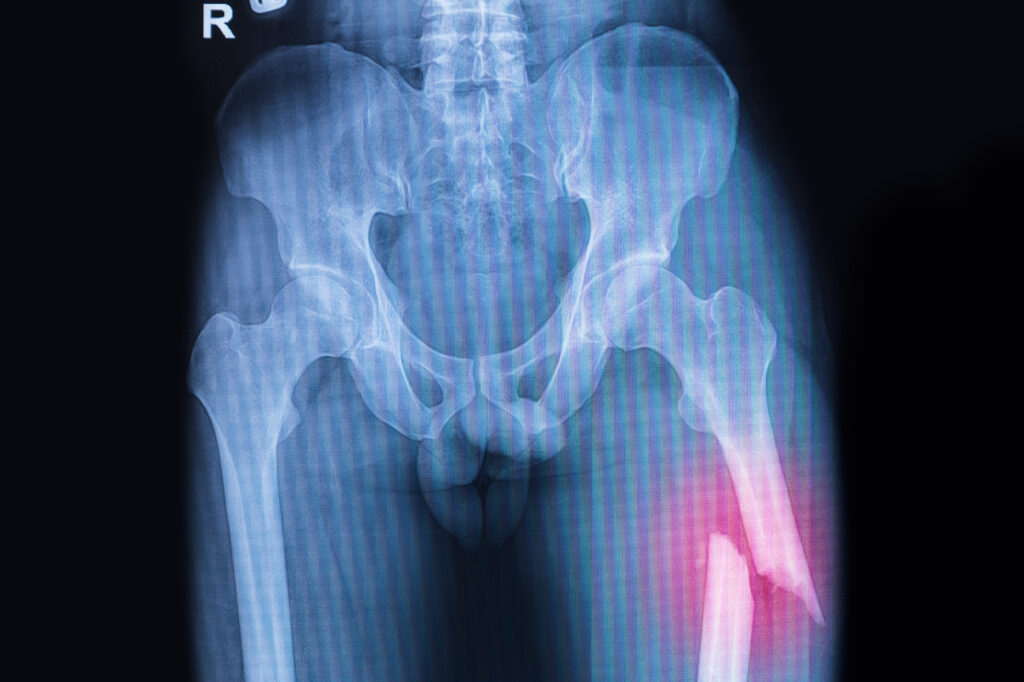

- Fractures